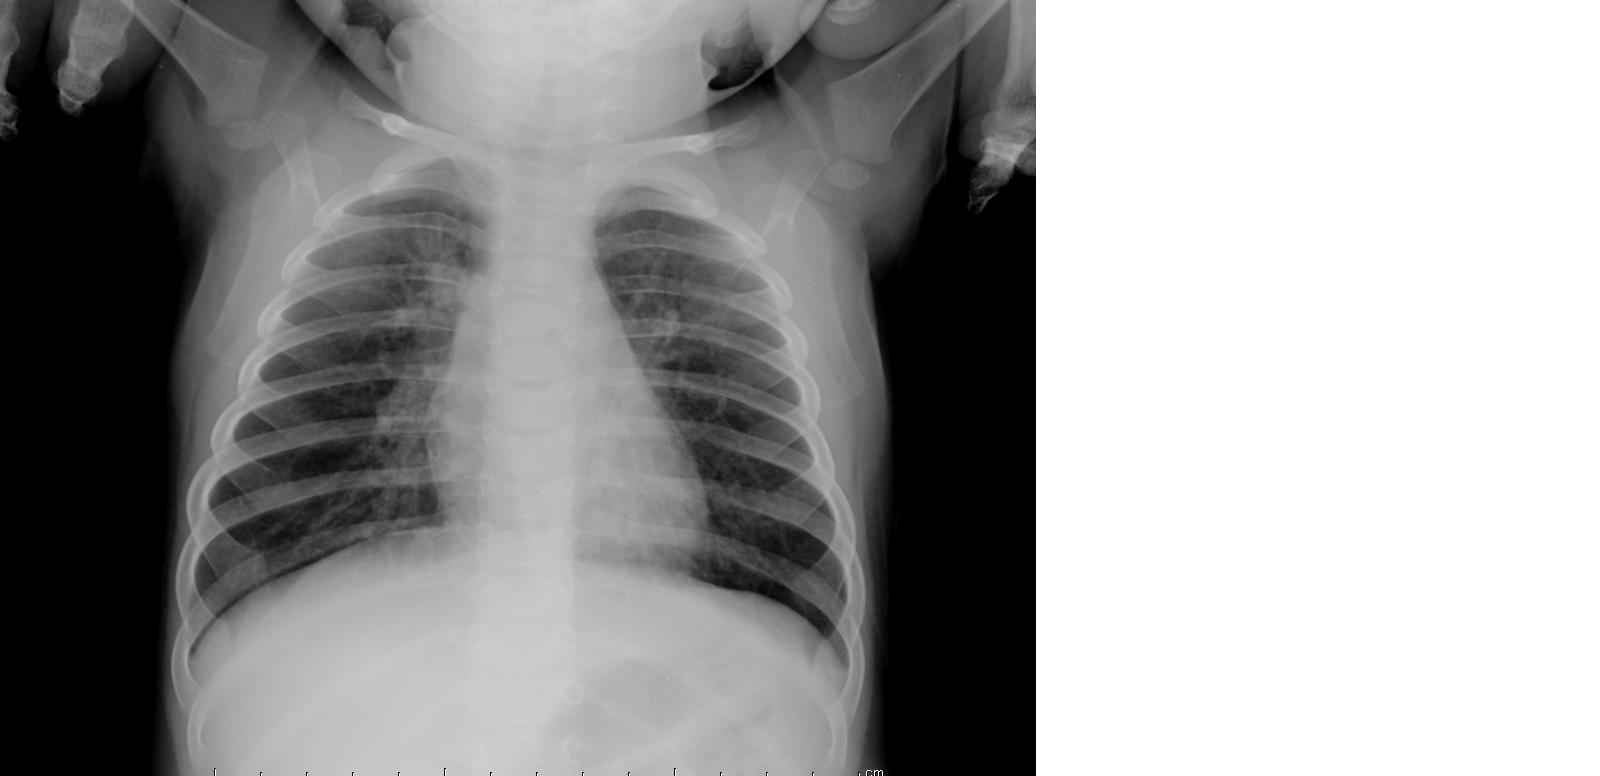

associati a crepitii fini tele-inspiratori diffusi. L�Rx del

torace (Figura 1) confermava la diagnosi di bronchiolite. Gli esami ematochimici

effettuati non mostravano alterazioni degli indici di flogosi.

Figura 1.